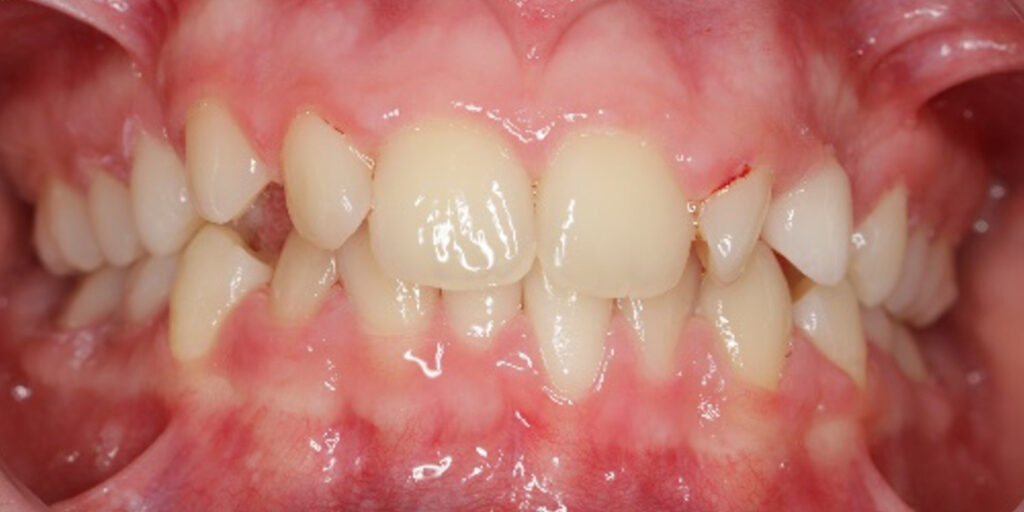

The 14-year-old female patient visited the orthodontic practice in February 2021. The chief complaint was that her upper arch was affecting her confidence in her smile. Upon examination, the patient was found to have a normodivergent facial pattern and a skeletal class II with mandibular retrusion. An intraoral examination revealed narrow arches, a class II molar and canine relationship, deep bite, retroclined upper and lower incisors, and retained teeth 63, 74, and 84.